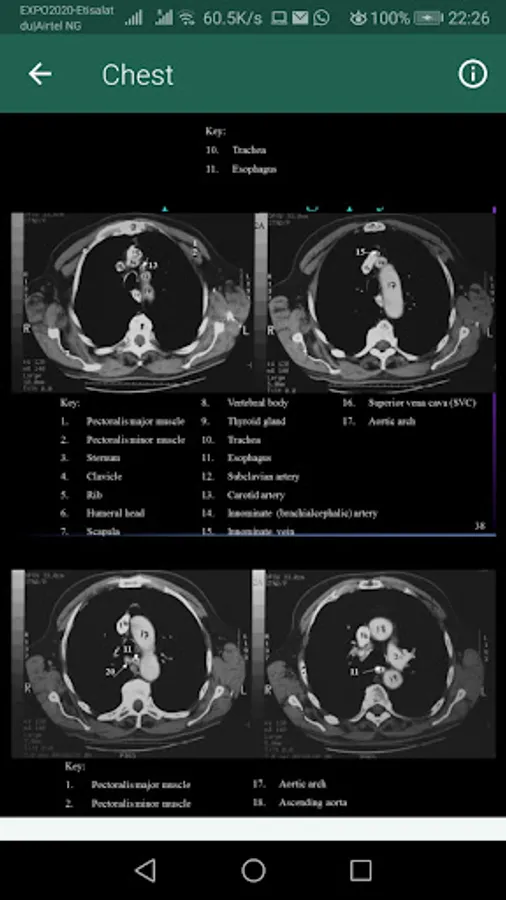

An ideal resource for the classroom or clinical setting, Sectional Anatomy for Imaging Professionals, the App provides a comprehensive, and highly visual approach to the sectional anatomy of the entire body. Side-by-side presentations of actual diagnostic images from both MRI and CT modalities and corresponding anatomic line drawings illustrate the planes of anatomy most commonly demonstrated by diagnostic imaging. Easy-to-follow descriptions detail the location and function of the anatomy, while clearly labeled images help you confidently identify anatomic structures during clinical examinations. In all, it’s the one reference you need to consistently produce the best possible diagnostic images.

Side-by-side presentation of anatomy illustrations and corresponding CT and MRI images clarifies the location and structure of sectional anatomy.

Reference drawings and corresponding scanning planes appear on appropriate pages with the actual images, so they are easily referenced for correlation between the scanning planes and the resulting images.